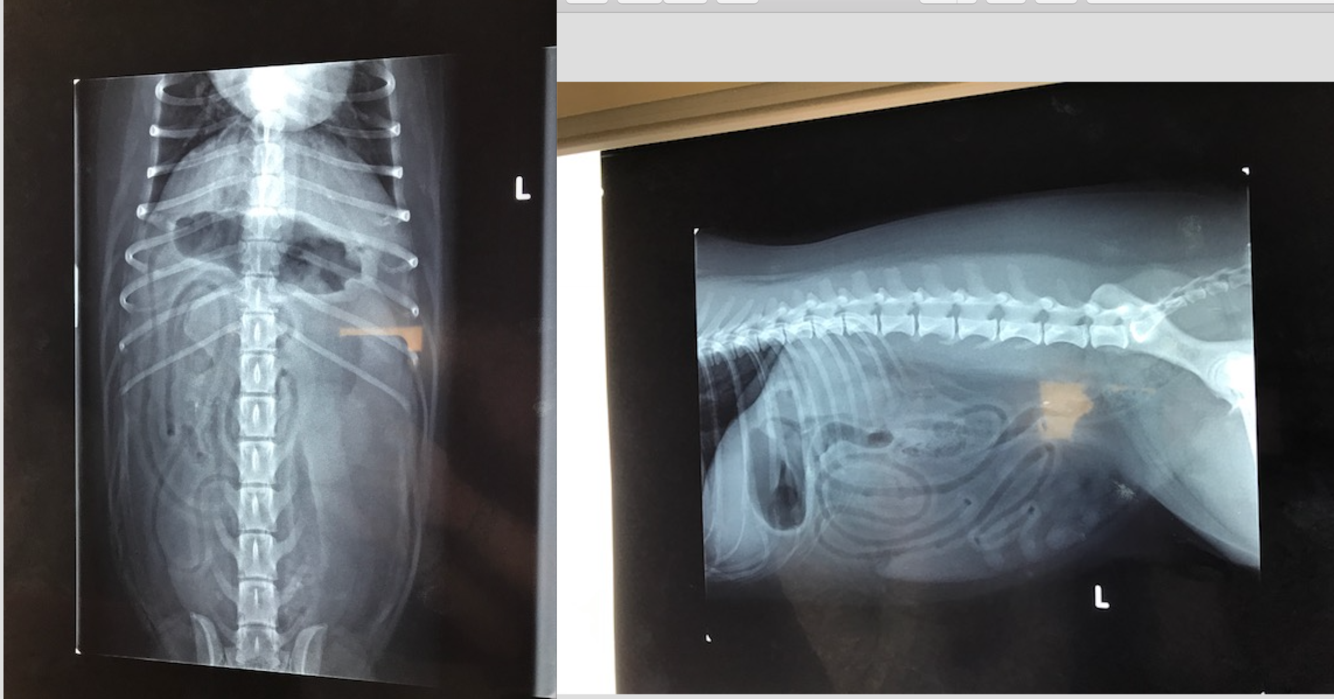

9 week old Male Labrador

Hx: Vomiting and anorexia for 2 days

HR 144 RR 36 Temp 39.7C NAD on abdo palpation

* Why decreased serosal detail?

* The gas within the GIT– which parts contain gas? Are the gas filled portions of the GIT over distended?

* The fluid filled portions– which parts contain fluid? Are they over distended?

* Which other organs can you ID? Are these within normal limits?

* What are your recommendations for further investigation and treatment of Baughie?